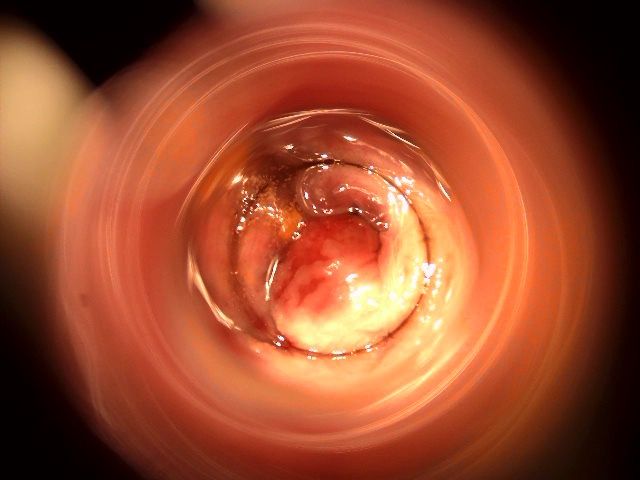

La cura delle emorroidi patologiche, finalmente senza dolore

Come Chirurgo Vascolare, sono perfezionata in Proctologia da molti anni, e molti altri ne ho passati direttamente in sala operatoria, praticando l'emorroidectomia con metodo Milligan-Morgan.

Durante la mia esperienza come Chirurgo Protcologo, ho visto personalmente come i trattamenti chirurgici disponibili, benché necessari, fossero comunque abbastanza invasivi per il paziente, specialmente nel decorso post operatorio.

Fortunatamente, negli ultimi anni sono stati messi a punto protocolli non chirurgici molto avanzati, che ho personalmente studiato ed approfondito con molto interesse.

Tra questi, ho cominciato ad utilizzare il trattamento sclerotizzante con scleromousse stabilizzata ad aria sterilizzata, che considero ormai il 'Gold Standard' per il trattamento non invasivo e permanente delle emorroidi patologiche.

Ho quindi attrezzato il mio studio con il moderno Videoproctoscopio Digitale, nonché con avanzate pompe miscelatrici ad aria sterilizzata, in grado di ottenere una scleromousse stabilizzata di grande qualità, perfetta per il trattamento emorroidale.

Grazie a questo protocollo, posso risolvere casi anche molto gravi di prolasso emorroidale, garantendo una risoluzione definitiva in oltre il 95% dei casi clinici.

Il tutto, senza il minimo dolore o disagio per il paziente.